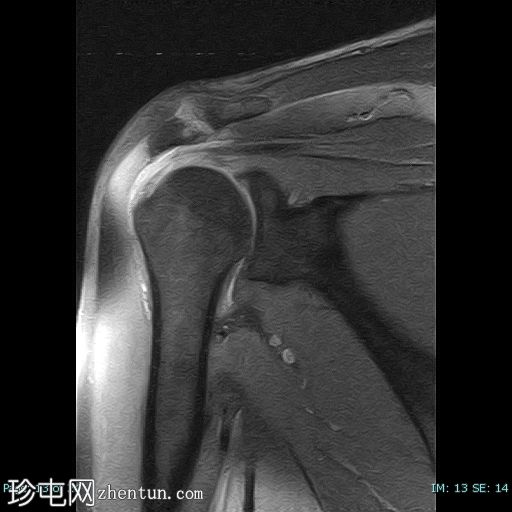

冠状位

T2

冈上肌腱前部纤维及肌腱止点-关键区交界处全层撕裂。撕裂间隙被T2/PD高信号液体填充。肌腱回缩2.1厘米,位于肩峰水平。

未见肱骨头骨内囊性改变或冈上肌腱神经节/黏液囊肿。

冈上肌腱变薄并伴有肌腱病,冈上肌脂肪变性为2级(Goutallier分级)。

本病例展示了退行性冈上肌腱撕裂的典型位置,即肌腱足印和关键区交界处。这与创伤性撕裂(通常发生在肌腱交界处)形成对比。

应注意,不应过度依赖质子密度加权成像序列来诊断肩袖撕裂,因为该序列容易出现魔角伪影,从而模拟撕裂。较长的回波时间序列(例如T2加权成像)可以有效避免这种假阳性结果。